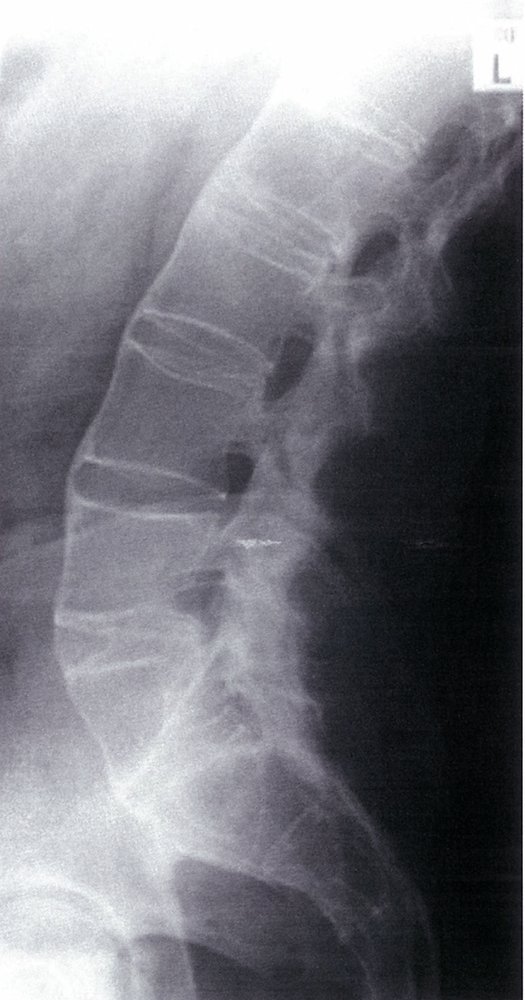

Spine (AP and lateral views)

• Indications

• Pain in the cervical, thoracic, or lumbar spine

• Suspicion of AS remains after a negative radiograph and MRI of sacroiliac joints

• Characteristic findings

• Loss of lumbar lordosis: abnormal straightening of the spine

• Ankylosis of costosternal and costovertebral joints

• Bamboo spine: seen in later stages and is caused by the following

• Ossification of outer fibers of the annulus fibrosus resulting in ankylosis (fusion) of intervertebral joints

• Syndesmophytesbetween adjacent vertebral bodies (see “Syndesmophytes vs. osteophytes”)

• Shiny corners sign: reactive sclerosis of the superior and inferior margins of vertebrae

Early stages of AS may be unidentifiable on x-ray (low sensitivity for early-stage). Hence, a patient with several classical clinical and laboratory findings fulfills the diagnostic criteria for AS even if x-ray findings are inconclusive. [5][15]